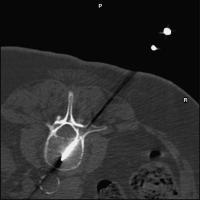

Vertebroplastie - Wirbelkörperpunktion

Abbildung 1: Transpedikulärer Punktionsweg

Keywords:

Lendenwirbelsäule

,

Mineralstoffwechsel

Röntgenbild

transpedikulär

Wirbelkörperpunktion